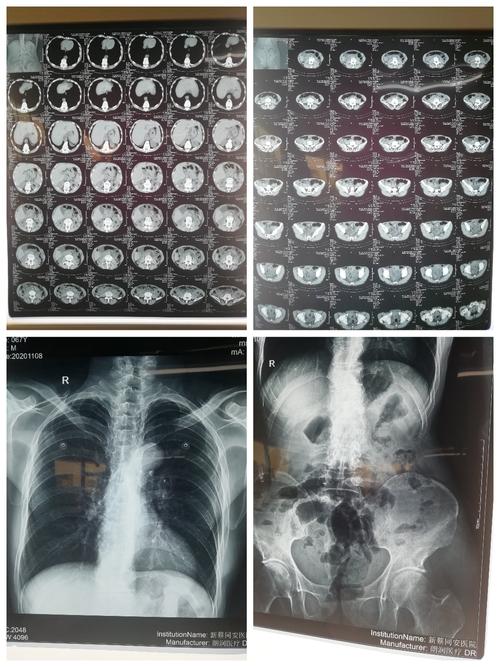

该病人腹部ct及胸腹部平片,未见气液平面.

肠梗阻腹部平片图片

肠梗阻腹部平片

肠梗阻腹部平片表现